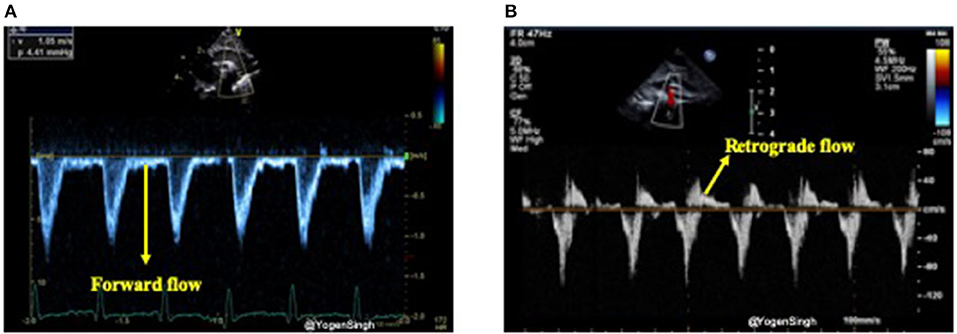

In the presence of a large PDA, blood shunts away from the systemic circulation throughout the cardiac cycle, however, this becomes more apparent during diastole and it can be studied using Doppler on echocardiography (15, 31). Retrograde or absent blood flow during diastole in descending aorta below the ductal ampulla or in the coeliac axis or superior mesenteric artery have been described as indicator of significant PDA shunt leading to systemic steal (systemic hypoperfusion) (24, 32). Doppler flow patterns from the descending aorta can be obtained from a suprasternal or high parasternal view with the pulsed wave Doppler sample gate placed distal to the origin of ductus arteriosus (ductal ampulla) (Figure 9).

Figure 9. Doppler assessment of blood flow in descending aorta (post-ductal flow). (A) Showing forward blood flow during disatole; and (B) showing retrograde blood flow during diastole indicating “ductal steal” in presence of a large PDA.